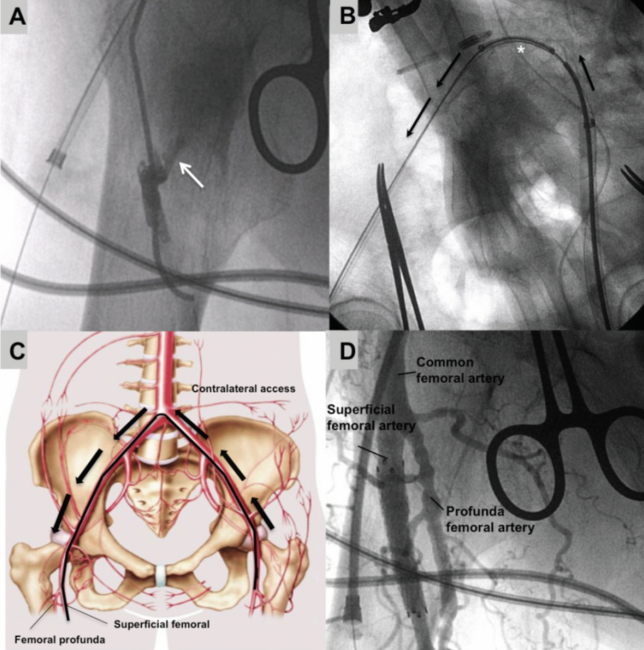

We present the case of a patient with severe aortic stenosis and an AVF between the right superficial femoral artery and the femoral vein, in which a percutaneous closure of the AVF was performed from the contralateral side using a covered stent, immediately after TAVI.

Coronary angiography ruled out coronary artery disease, showing an AVF between the superficial femoral artery and the femoral vein (Figure 1; Videos 1-3). Transfemoral TAVI was performed with direct implant of a 23 mm SapienXT valve (Edwards Lifesciences) advanced through the left femoral artery. After that, percutaneous closure of the AVF was achieved implanting a Fluency stent (Bard) from the contralateral side (Figure 2; Videos 2-5).